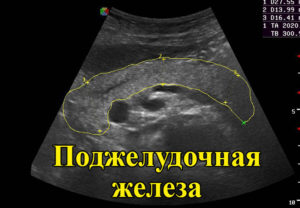

При ультразвуковом сканировании врач в норме будет видеть “колбасовидную”, S-образную форму поджелудочной железы.

Она будет иметь четкие и ровные края, иметь гомогенную, мелкозернистую или же крупнозернистую структуру, на экране будет виден без деформаций сосудистый рисунок, центральный проток железы – Вирсунгов проток не будет увеличен (в норме – 1,5-2,5 миллиметра). Он имеет вид тонкой гипоэхогенной трубки, может уменьшаться в диаметре в хвосте и быть больше в области головки железы.

Показателем здоровой поджелудочной железы является ее однородная структура.

У взрослого человека ее размеры головки железы могут быть от 18 до 30 миллиметров, тела – от 10 до 22 миллиметров, а хвоста – от 20 до 30 миллиметров. У детей все будет зависеть от роста, веса и возраста ребенка: тело от 7 до 14 мм, головка железы от 12 до 21 мм, а хвост от 11 до 25 мм.